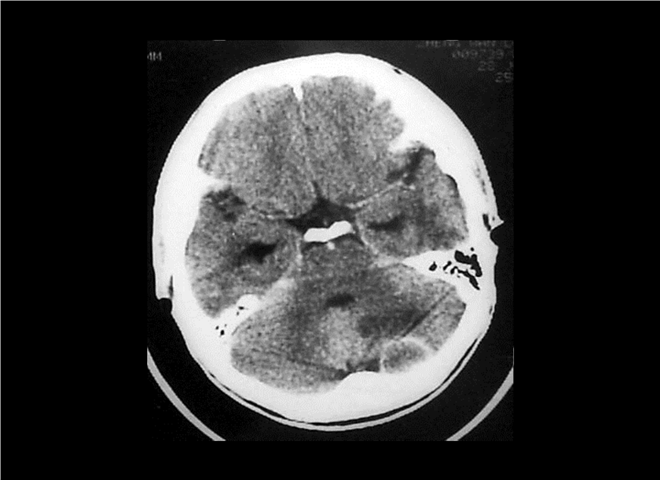

13_CT增强扫描